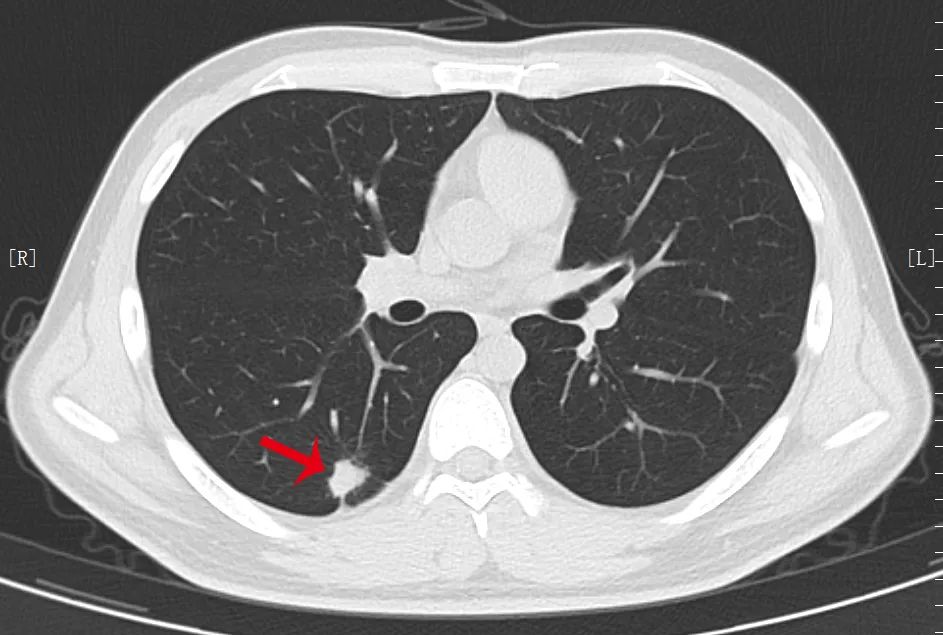

根据肺结节的密度将其分为三大类:实性结节、磨玻璃结节、部分实性结节,密度不一样,高危结节大小的评判标准也不同,>1.5 cm 的实性结节或者>8 mm 的部分实性结节。

长相越是古怪的结节,越需要高度重视,尤其是出现分叶、毛刺、胸膜牵拉、含气细支气管征和小泡征、偏心厚壁空洞等征象。